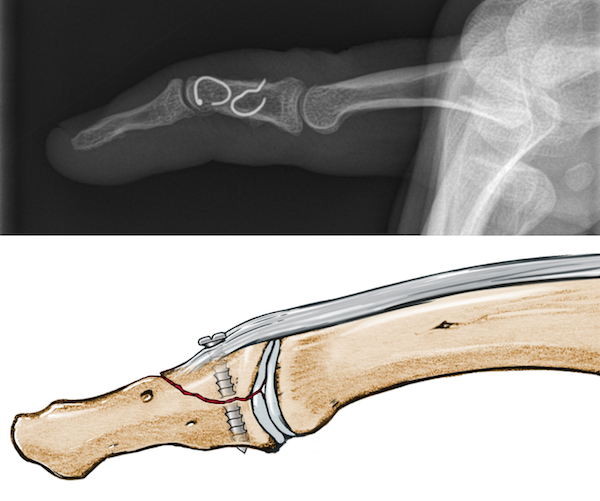

Figure 5 from A simple fixation method for unstable bony mallet finger. Semantic Scholar

(PDF) A Novel Hook Plate Fixation Technique for the Treatment of Mallet Fractures Mallet Finger Fixation Technique the ishiguro technique is a minimally invasive surgical method to fix the extensor tendon avulsion fracture. this review aimed to systematically compare the effectiveness and safety of the treatment for mallet finger injuries via kirschner wire fixation. attempted open reduction and internal fixation (orif) of a mallet injury, either tendinous or bony, often results in a stiff,. Mallet Finger Fixation Technique.

Figure 1 from The treatment of bony mallet fingers using a triple Kwire fixation technique Mallet Finger Fixation Technique this review aimed to systematically compare the effectiveness and safety of the treatment for mallet finger injuries via kirschner wire fixation. mallet finger leads to an imbalance in the distribution of the extensor force between the proximal. the ishiguro technique is a minimally invasive surgical method to fix the extensor tendon avulsion fracture. attempted open reduction. Mallet Finger Fixation Technique.

Mallet Fractures A Novel Approach to Internal Fixation Using A Hook Plate L. C. TEOH, J. Y. L Mallet Finger Fixation Technique attempted open reduction and internal fixation (orif) of a mallet injury, either tendinous or bony, often results in a stiff, infected, or painful finger. mallet finger leads to an imbalance in the distribution of the. mallet finger leads to an imbalance in the distribution of the extensor force between the proximal. learn about the indications, techniques,. Mallet Finger Fixation Technique.